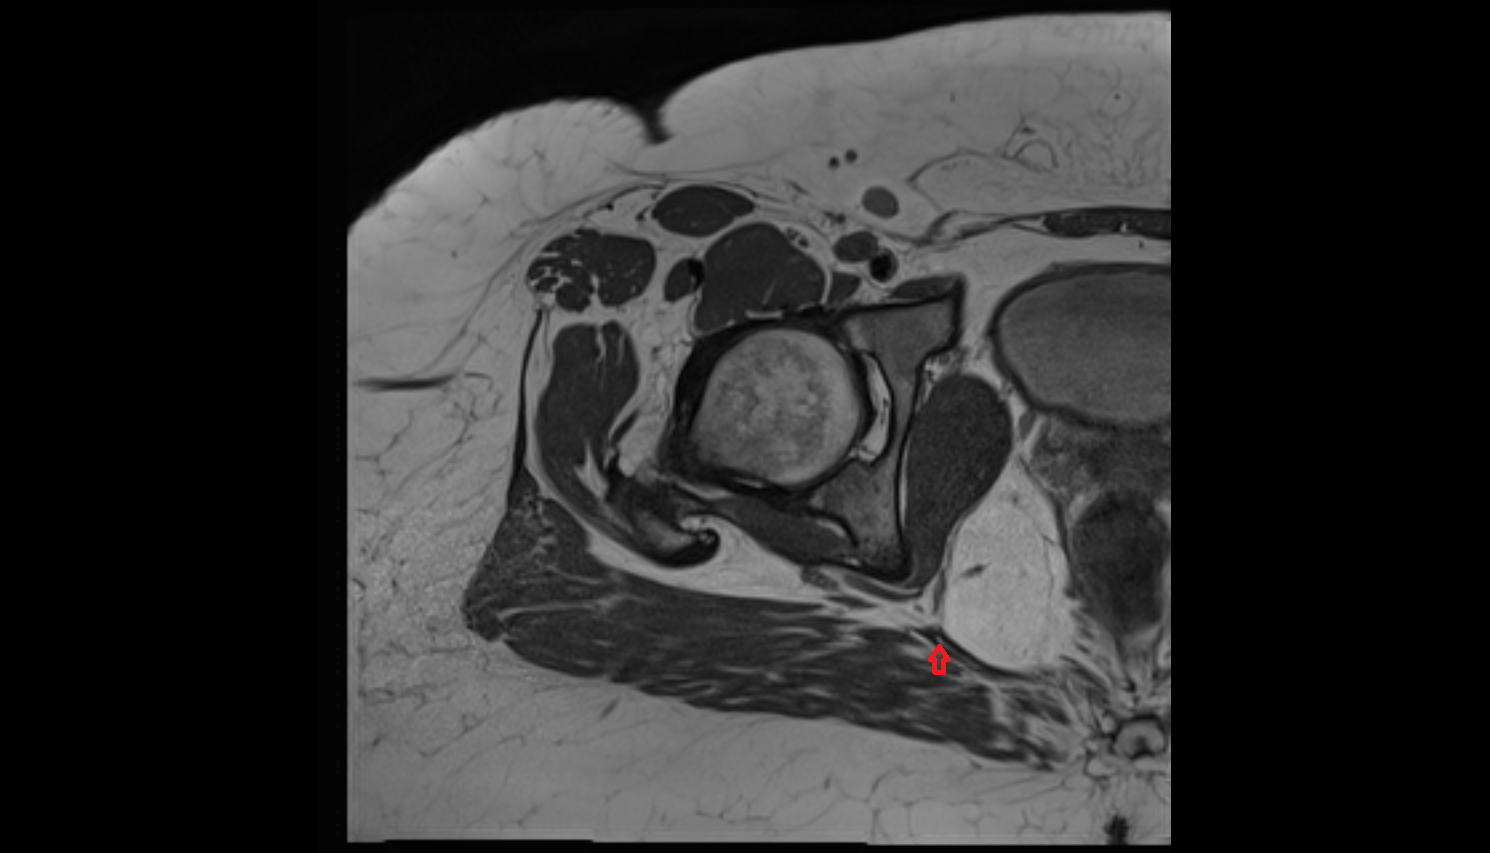

- Uterus

- Vagina

- Rectum

- Urinary bladder